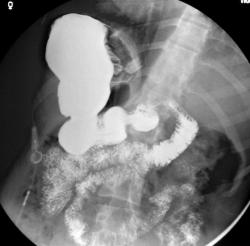

Не, тоже не то. верхние снимки выполнены в положении стоя, последние в положении лёжа. Подсказка есть в самих снимках. Я извиняюсь за качество; у меня флюроскопия записывается в виде цифрового видео, пришлось "ловить стоп-кадры для публикации.

Общая брыжейка-да, наиболее вероятно. Но не это главная причина, по которой я опубликовал данное наблюдение. Инверсии нет; я уже указал что снимки это стоп-кадры с записи флюорографического исследования, поэтому получается зеркальное изображение. В случае инверсии, я конечно бы разместил обзорный снимок. Патология исключительно в желудке, и это наглядно видно. Я понимаю что "играю-немного-не-по-честному", но я сразу указал что это именно загадка. "Подсказка"-это не дренаж; пациентка пришла амбулаторно.

Валентин Львович, дело не в вдавлениях по медиальному краю; и конечно адекватная оценка состояния желудка невозможна без минимума стандартных проекции. Но, вся информация на основании которой можно догадаться о правильном ответе, есть на представленных снимках.

Не, тоже не то. верхние снимки выполнены в положении стоя, последние в положении лёжа. Подсказка есть в самих снимках.

Общая брыжейка-да, наиболее вероятно. Но не это главная причина, по которой я опубликовал данное наблюдение. Инверсии нет; я уже указал что снимки это стоп-кадры с записи флюорографического исследования, поэтому получается зеркальное изображение. В случае инверсии, я конечно бы разместил обзорный снимок.

Патология исключительно в желудке, и это наглядно видно. Я понимаю что "играю-немного-не-по-честному", но я сразу указал что это именно загадка. "Подсказка"-это не дренаж; пациентка пришла амбулаторно.